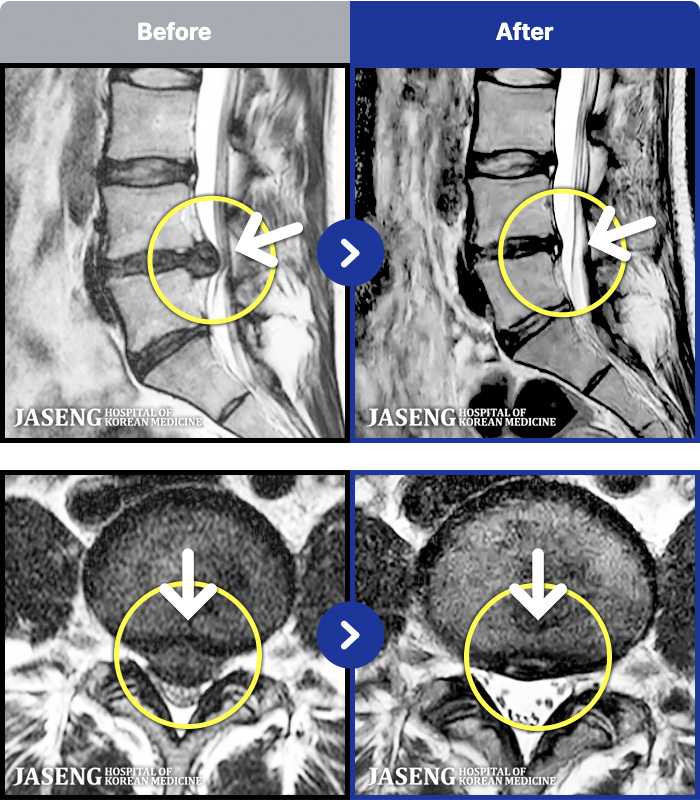

1,287 MRI ũ ʸ Ȯϼ.